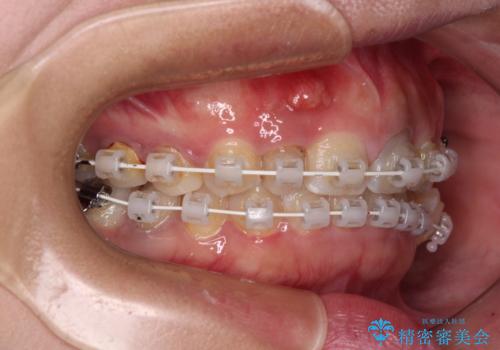

歯列から飛び出た歯 ワイヤー矯正で整った歯列に

- 下顎の歯列から飛び出した小臼歯を気にして来院された患者様です。

歯列以外に、上顎左右側切歯が矮小歯であり、上顎4前歯は失活していたため、矯正治療で歯列を整えるとともに上顎前歯の幅を調整し、矯正治療後にオールセラミッククラウンにて審美歯科治療を行うこととしました。

矯正治療は、小臼歯1本分を歯列に納めないいけない状態であったため、表側のワイヤー装置にて行うこととしました。